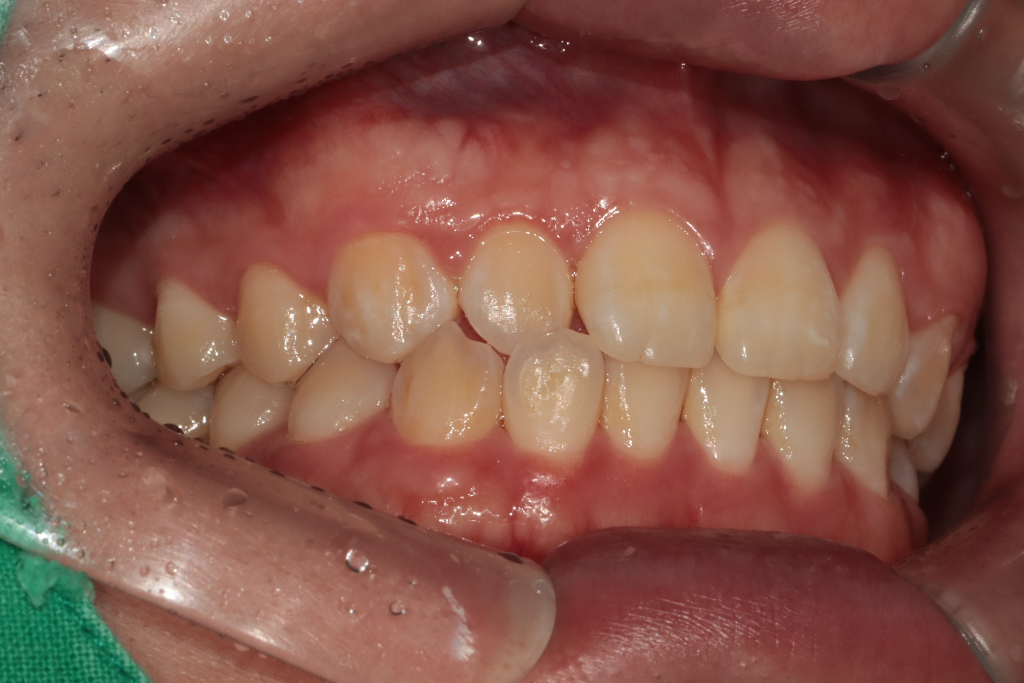

상악이 덜 발달된 것으로 보여집니다. 정확한 것은 임상사진을 통해서 연조직과의 관계도 파악해야 하며 현재 자료의 단편적인 것으로 평가하지 않습니다. 얼굴 및 신체는 3차원적이기 때문에 임상사진 및 방사선 사진 그리고 여러가지 검사 등을 통해 최종 확진하므로 치과 교정과 방문 후 상담을 해보시길 바랍니다.

하악 골격이 발달되어서 치아가 나와보이는 거나 아니면 돌출입처럼 보이는걸까요?

-하악골격이 발달되면 흔히 말하는 주걱턱처럼 보이게 됩니다. 돌출입은 치아보다는 골격적인 이유가 큽니다.

상악이나 하악이 정상범위보다 많이 발달되어있는 건가요?

-많이 발달됫다기 보다는 정상범주에서 벗어낫다고 보시는게 맞을것같습니다.

개선을 원한다면 교정만으로는 무리인가요?

-골격적으로 이상이 있다면 교정만으로는 효과를 볼수 없습니다.